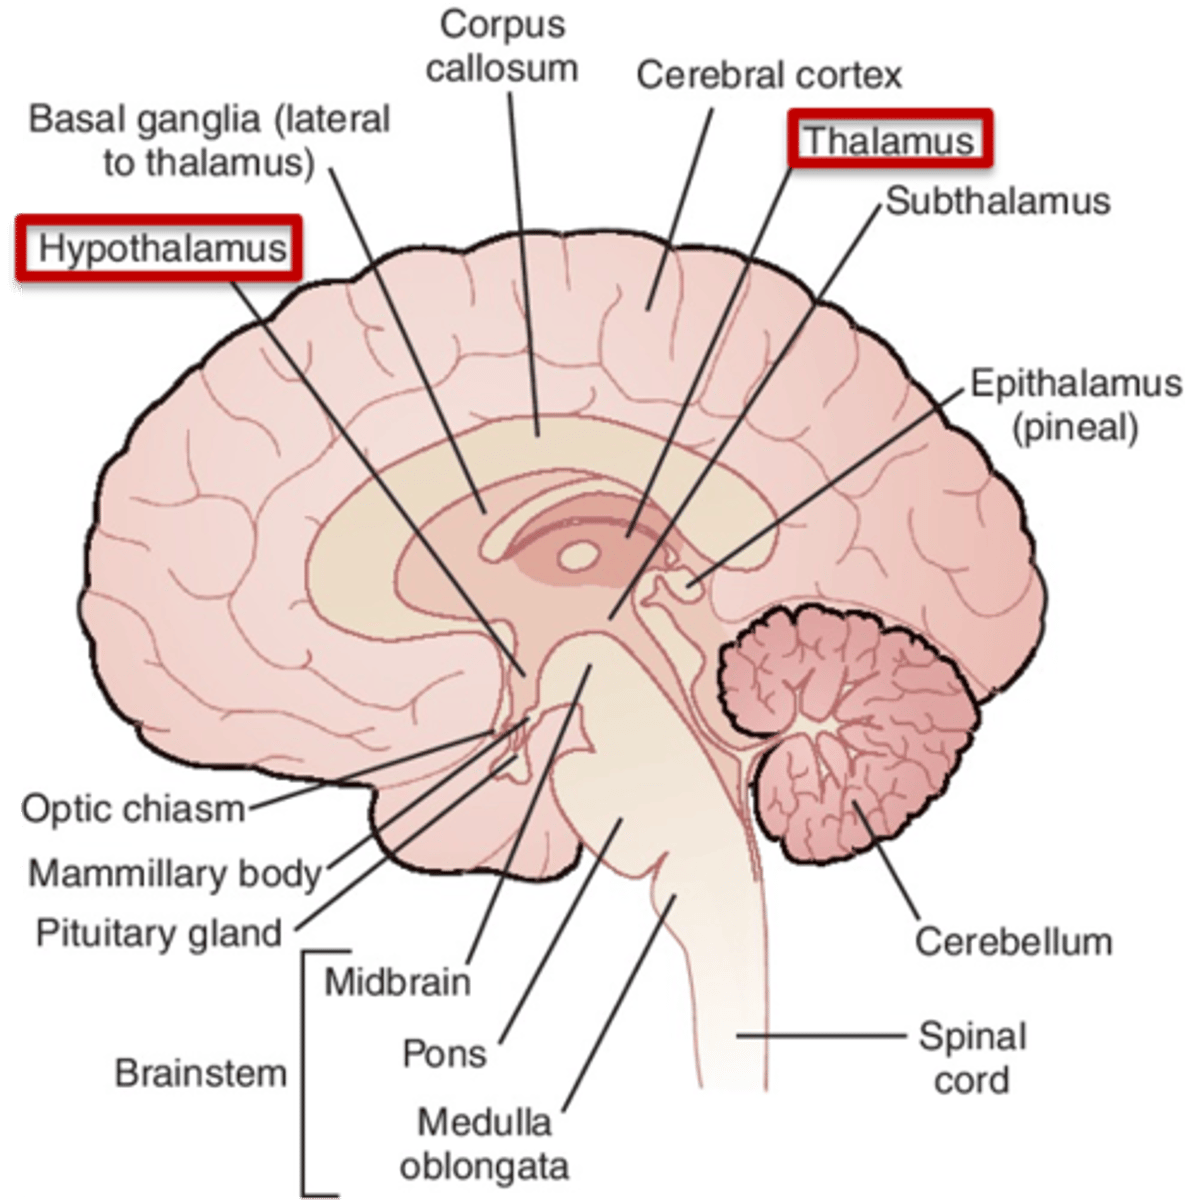

what are 2 important structures of the diencephalon?

1. thalamus

2. hypothalamus

what structure of the diencephalon regulates the of flow sensory and motor information from various location that will ultimately reach the cortex?

thalamus

what structure of the diencephalon is the relay station for all but one sensory tracts on their way to the cortex? what is the exception?

thalamus

olfactory is the only tract to bypass the thalamus and go directly to the cortex

what are 2 key thalamic nuclei?

1. ventral posterolateral nucleus (VPL)

2. ventral posteromedial nucleus (VPM)

what structure of the diencephalon is the main visceral control center of the brain?

hypothalamus

what structure of the diencephalon mediates a wide range of functions through connections with endocrine, autonomic, somatic motor, limbic systems, and maintaining a state of homeostasis?

hypothalamus